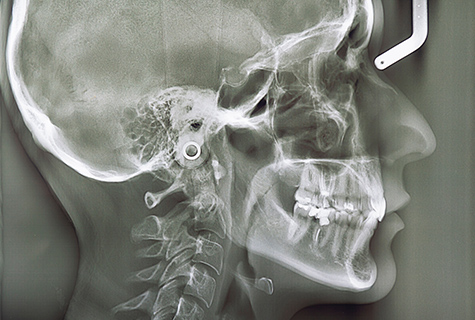

矯正治療を行うためには、事前にしっかり検査して綿密な治療計画を作成することが大切です。当院では、セファロや口腔内スキャナー、加速装置(PBM)など各専用設備を導入しています。これらの設備を活かして、精密検査を実施いたします。

02 精密検査

矯正治療を進めるにあたり、まずは患者さんの口周りをチェックします。口腔内スキャナー(シリオス)などの専門設備を用いて精密検査を実施し、歯や骨の状態を確認させていただきます。